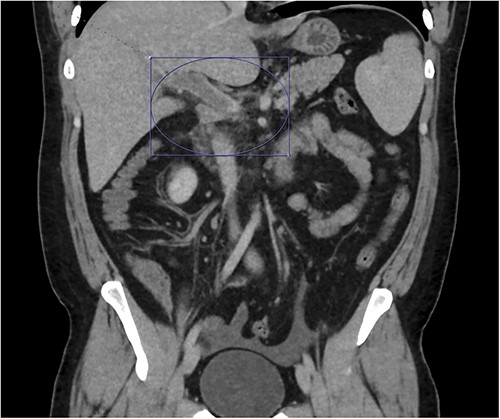

On presentation to the emergency department (ED), he was afebrile and normotensive with blood pressure in the 120s/80s though he had sinus tachycardia (heart rate 120–130 s). His abdomen was soft and diffusely tender with point tenderness at McBurney’s point and negative Rovsing’s sign. He had no signs of frank peritonitis. His complete blood count revealed leukocytosis (WBC 11K/μl), lactic acidosis (lactate 3 mmol/l), and mild transaminitis with AST 72 and ALT 101. An intravenous (IV) contrast-enhanced computed tomography scan of the abdomen/pelvis demonstrated a mildly dilated appendix (~8 mm) with surrounding fat stranding but no appendicolith, perforation, or abscess (Fig. 1). Interestingly, a partial portal vein (PV) and superior mesenteric vein (SMV) thrombosis were also noted (Fig. 2). Initial blood cultures were collected, which remained without growth.

Thrombosis can be seen extending into the mesenteric venous system as well as the intrahepatic portal veins; associated mesenteritis and abdominal ascites (not well visualized) are also seen.

Patient was admitted to the surgical service and started on broad-spectrum IV antibiotics (piperacillin–tazobactam) and was made nil per os. He was resuscitated intravenously with 2 l of crystalloid. Given the thrombosis of his PV and SMV, the patient was initiated on systemic anticoagulation with IV heparin which achieved therapeutic dosing within 24 hours. Over the course of the next few days, his abdominal pain and tachycardia improved. Interval CT abdomen/pelvis scan 5 days from presentation demonstrated progression of the thrombus to involve lobar, segmental, and subsegmental portal venous branches as well as the splenic vein distal to the portosplenic confluence (Fig. 2).